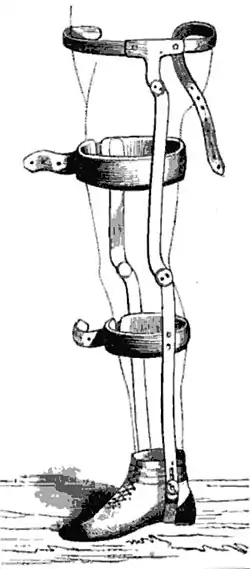

Dans le traitement conservateur, on essaie de compenser précocement l'instabilité fonctionnelle du mouvement par un traitement d'entraînement musculaire étudié, et ainsi de rétablir la stabilité manquante. Un but plus lointain est l'amélioration des sensations proprioceptives des éléments situés autour de l'articulation (périarticulaires)[138],[139],[140]. Souvent, on atteint une stabilité suffisante avec un maintien de l'articulation en position par une orthèse Knie-brace pendant six semaines, accompagné d'une physiothérapie.